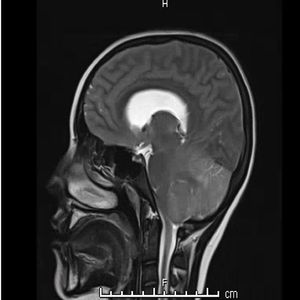

13-year-old female with altered mental status, headache and emesis. What is the diagnosis?